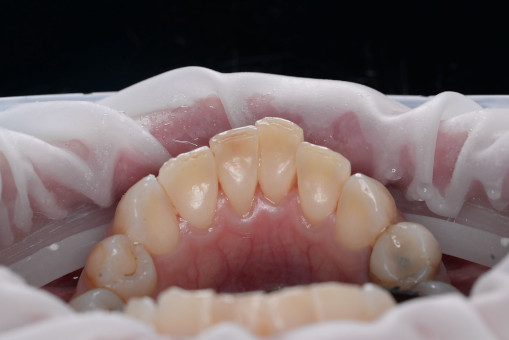

А прежде, чем вы посмотрите фотографии «до» и «после» лечения слизистой оболочки полости рта, проведенных в нашей клинике, хочу поблагодарить большое количество наших пациентов, которые поверили, прониклись нашей концепцией, и мы вместе, именно вместе победили болезни десны, гингивит и пародонтит!

До/после лечения